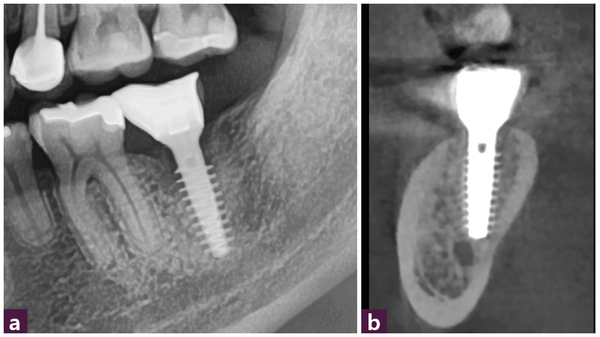

23세 남성 환자가 37번의 극심한 통증으로 내원했다. 해당 치아의 발치가 필요했으나 mandibular canal까지 거리가 3mm 정도로 가까워 safety margin을 확보하기가 어려운 상황이었다. [그림 1]

37번 치아의 치근 형태는 근원심 치근이 붙어 있는 one root 형상이었으며 근심쪽으로 잔존골이 매우 부족한 상황이었다. 이처럼 불리한 조건에도 불구하고 발치 후 즉시 식립을 계획한다면 37번의 근심과 mandibular canal 상방 및 lingual cortical plate에서 고정을 기대할 수 있었다. [그림 2]

본 증례에서는 3mm 정도의 잔존골에 1~2mm의 식립구를 형성해 MagiCore의 마지막 나사산을 잔존골에 engage 시킬 수 있었다. 초기 식립 토크값(initial torque value)은 35Ncm이었다. 신경관 근처 부위의 식립구 형성과 식립 후 확인은 portable standard 촬영을 통해 확인했다. [그림 4]